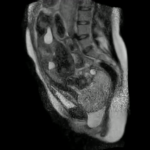

MRI Of Childbirth Shows Miracle Of Life From The Inside Out

For thousands upon thousands of years, we humans got to witness the blessed spectacle of childbirth from only one vantage point. But now, thanks to the wonders of magnetic resonance imaging technology, or MRI, we can see what’s actually going on. Putting a soon-to-be mom inside an MRI scanner isn’t some harebrained idea. The point of the experiment, at least when German … [Read more...] about MRI Of Childbirth Shows Miracle Of Life From The Inside Out